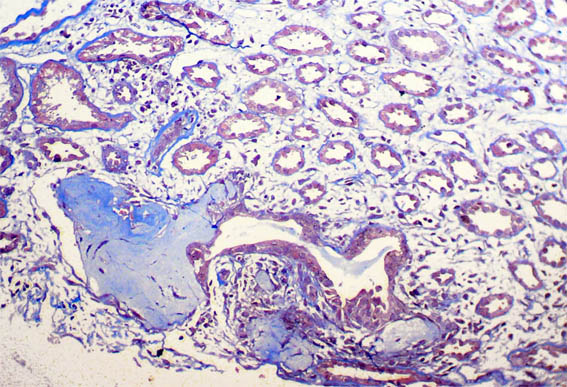

Figura 2.

Tricrómico de Masson, X100.